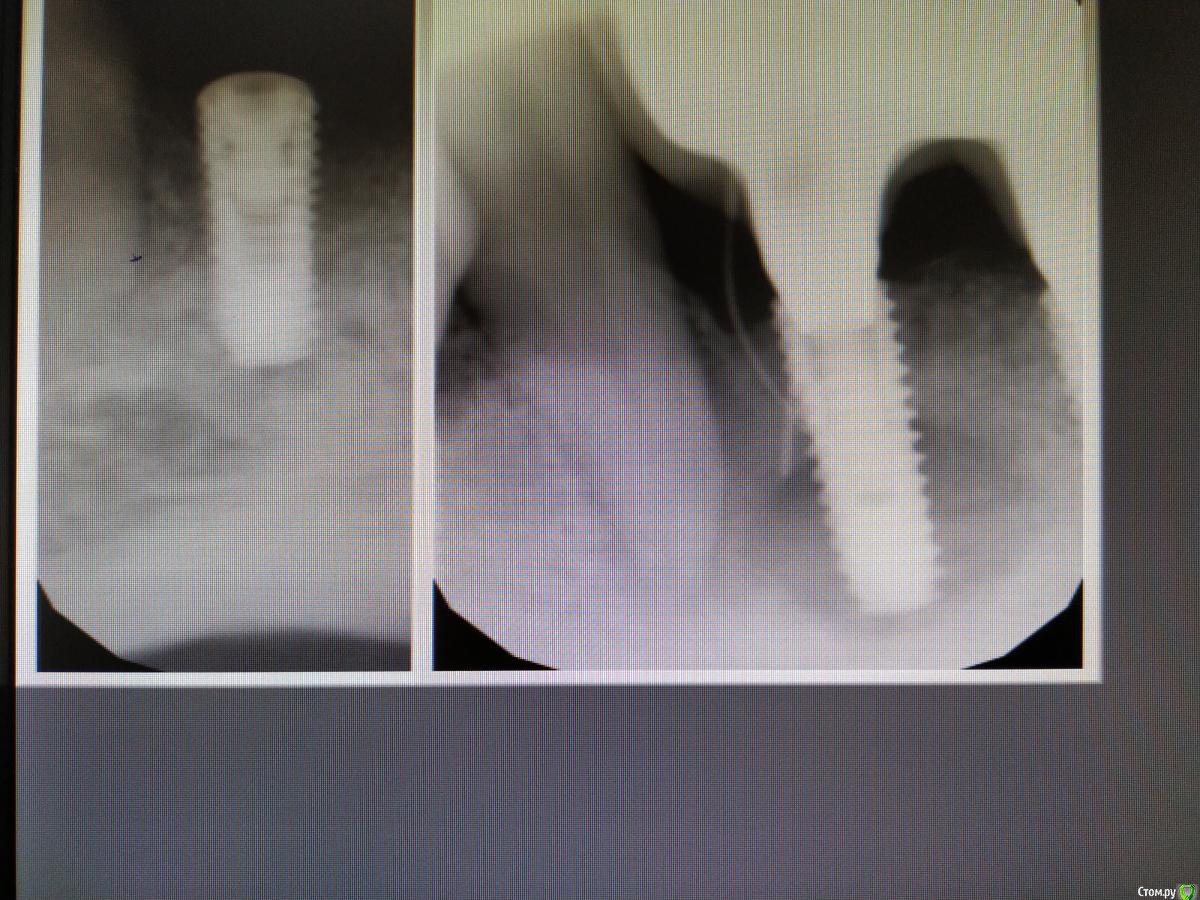

gum Опубликовано 18 марта, 2019 Поделиться Опубликовано 18 марта, 2019 (изменено) Здравствуйте. Год назад установлено 8 имплантатов (Осстем). В том числе в области 32, 42 и соответственно мостовидный протез с опорой на 32-42. Ничего не беспокоило. Пациент обратился с совершенно другой проблемой. При осмотре наблюдаю свищевой ход в области 42. Делаю снимок и... результат на лицо, то есть на экране.То что удалять его это понятно. Вопросы такие: 1. Что можно сделать в качестве временной конструкции кроме съемного протеза (мб есть какие-либо варианты)?2. В чем может быть причина?Снимок-фотография с экрана, поэтому размыто слегка. Изменено 18 марта, 2019 пользователем gum Ссылка на комментарий

Дмитрий Л. Опубликовано 18 марта, 2019 Поделиться Опубликовано 18 марта, 2019 (изменено) Доктор, у вашего пациента хронический гранулирующий периодонтит от зуба. Я бы удалил зуб, хорошенько бы отмыл всё, и оставил имплантат. Есть шансы что имплантат удастся сохранить. В самом "трешевом" варианте мы можем обойтись эндодонтией зуба. Изменено 18 марта, 2019 пользователем Дмитрий Л. Ссылка на комментарий

gum Опубликовано 19 марта, 2019 Автор Поделиться Опубликовано 19 марта, 2019 Я подумал, что изменения в область верхушки 43 это вторично, от периимплантита.Вы считаете, что после устранения периодонтита возможно образование кости в области имплантата? Ссылка на комментарий

Дмитрий Л. Опубликовано 19 марта, 2019 Поделиться Опубликовано 19 марта, 2019 Я считаю, что периимплантит является осложнением периодонтита. Поверхность уже контаминирована, но шансы есть. При чем я бы не стал играться с винтом в плане чистки или шлифовки, для этого потребуется слишком инвазивный доступ. Удалить зуб, отмыть хорошо, антибиотикитерапия и наблюдать. Если имплантат подвижен то это конечно же не сработает. А потом на случай удаления винта можно предложить имплантацию в области клыка (который мы удалим) с немедленной нагрузкой, но надо ли оно в жевательном отделе. Ссылка на комментарий